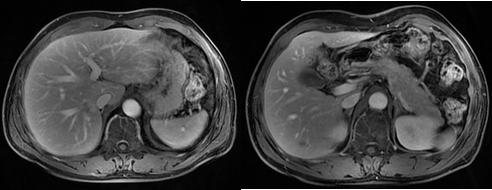

MR示肝多发转移(2019.10)

MR示经治疗后病灶明显缩小(2019.12)